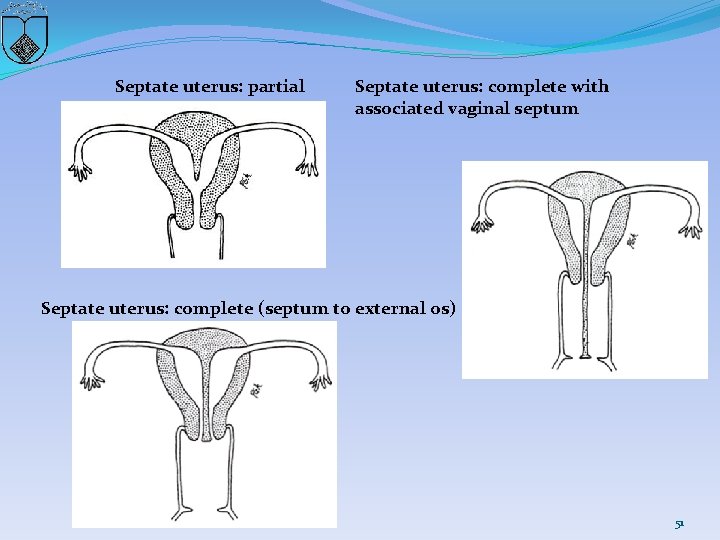

Lateral fusion defects �Lateral fusion defects are the most common type of müllerian defect. �The resulting organs are either symmetric or asymmetric, and obstructed or nonobstructed. �These fusion defects result from failure of formation of one müllerian duct, migration of a duct, fusion of the müllerian ducts, or absorption of the intervening septum. �Defective resorption of the tissue between the fused müllerian ducts results in a uterine septum, which may extend either partially down the uterus or the full length to the cervix. � A septum is the most common type of uterine defect 48

Septate uterus: partial Septate uterus: complete with associated vaginal septum Septate uterus: complete (septum to external os) 51